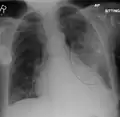

AP CXR showing right lower lobe pneumonia -